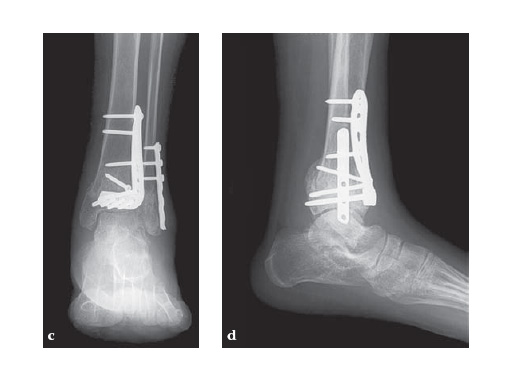

The LCP Anterolateral Distal Tibia Plates 3.5 are indicated for fixation of fractures, osteotomies, nonunions and malunions of the distal tibia, particularly in osteopenic bone, and in cases with bad soft tissue or wounds at the anteromedial side. The plate has a 60 twist in the shaft to fit to the distal tibia anatomy. The plate width in the shaft was increased, and a proximal hole added for compression or distraction with the articulated tension device. The 3.6 mm shaft thickness tapers to 2.5 mm distally. The plate has a low profile which is optimal for the anterior surface of the distal tibia with little soft-tissue coverage.

An increased variety of distal screw options enables screw placement according to the fracture pattern. 4 distal head screw holes are angled 7 inferiorly to capture the posterior malleolus, Volkmans triangle and the Chaput fragment. 3 K-wire holes in the head, parallel to the joint, accept 2.0 mm K-wires to temporarily fix the plate to the distal tibia, temporarily reduce articular fragments, and show proximity to the joint.

Clinical case:

28-year-old woman had a high energy motor vehicle collision and sustained an isolated distal left tibial fracture.